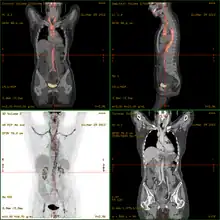

Severe vasculitis of the major vessels, displayed on FDG-PET/CT

• 18F-fluorodeoxyglucose positron emission tomography/computed tomography (FDG-PET/CT)has become a widely used imaging tool in patients with suspected Large Vessel Vasculitis, due to the enhanced glucose metabolism of inflamed vessel walls.[15] The combined evaluation of the intensity and the extension of FDG vessel uptake at diagnosis can predict the clinical course of the disease, separating patients with favourable or complicated progress.[16]